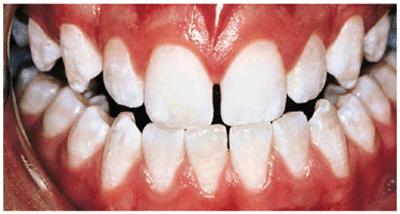

Figure 16-2A and B: Total neglect resulted in severe staining

of this patient's teeth.